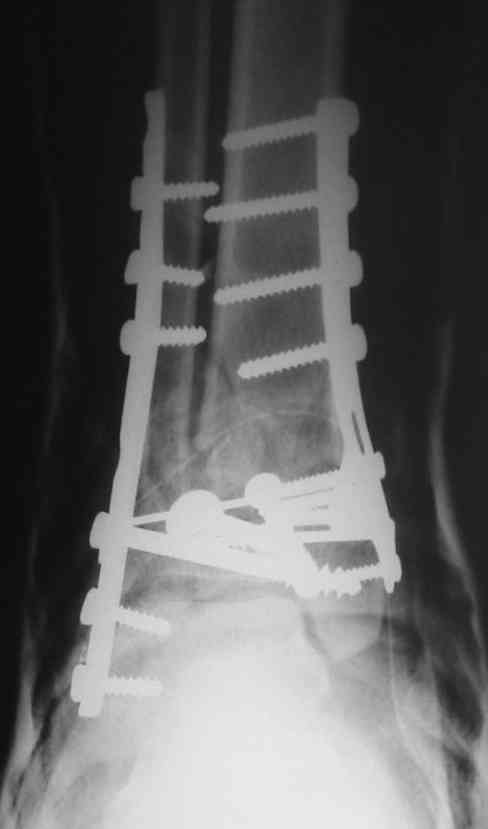

OK, Dr Driagin, Ja operiroval bolnogo po Vashemu, hotia sam ni ochen' ubezden' v itom, t.k. bolnoi otkazalsa na proch' ot ex.fix, ja emu sdelal ORIF + Kostnia plastika, snimky prelogiottsa,

Очень прилично получилось, но мне показалось, что винты на 4,5 мм.Это принципиально винты используются 3,5 и 4,0 мм. И проекцию прямую бы переделать. С уважением Дрягин

На представленном снимке видно, что эпифиз смещен латерально.

Пластина лист клевера есть в варианте DCP -динамическая компрессирующая пластина.В ней все отверстия круглые,развальцованные отверстия под винт 3,5, чтобы шляпка винта не торчала.Винты 4,5 тоже проходят в эти отверстия, но шляпка не погружается.Могут быть проблемы с мягкими тканями.Пластина LCP -пластина с блокированием.В каждом отверстие пластины нарезана резьба и на шляпке винта такая же.Получается блок винт-пластина-кость.Очень крепко.Первоначально она готовилась для остеопороза, много лет в Давосе её разрабатывали.Я видел там первые образцы ещё в 1995 году, а начали они в 80-годах.Насчёт оси по рентгенограмме пока не согласен пусть сделают хорошую, правильную прямую проекцию.С уважением Дрягин

Однозначно сказать сложно.Расстояние между тараном и медиальной лодыжкой меньше чем между тараном и крышей большеберцовой кости.Это может быть за счёт не правильной укладки.Пока не отчаиваетесь.Главное вы поняли принцип.Сделайте несколько проекций прямых и посмотрим.Для всех интересно.С уважением

Мне кажется, что все конечно далеко от идеала. Сложный перелом. Есть ощущение, что малоберцовая кость (ключ!) фиксирована с ротацией и удлинением. Снимки конечно необходимо сделать в правильных проекциях и без гипса...

В голеностопном суставе обязательны 3 стандартные ренгенологические проекции: прямая, латеральная и мортиз. Без них невозможно трактовать состояние голеностопа.

Применение шурурпов 4.5 мм и более толстых пластин крайне недопустимы. Рекомендуется низкопрофильные, контурированные пластины с шурупами 3.5 мм, а иногда те же 3.5 шурупы но с головкой 2.7 мм.